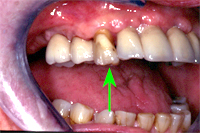

Die Teilprothese wurde während der Einheilphase der Implantate provisorisch getragen und jeweils angepasst. Die Patientin war nie ohne Zähne. Abb. 2 zeigt die dreigliedrige Fontbrücke auf zwei Implantaten zementiert und zwei Seitenzähne auf zwei Implantaten zementiert. Der eigene Eckzahn zwischen den beiden Implantatbrücken konnte erhalten werden (Abb. 3, grüner Pfeil).